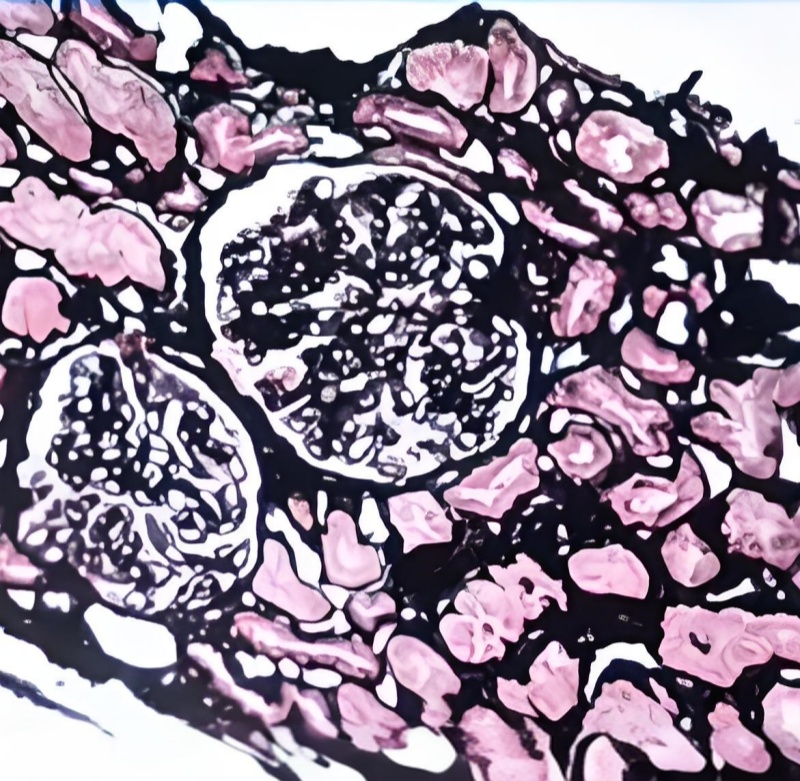

六胺银染色(神经内分泌细胞)

六胺银染色(Gomori Methenamine Silver Stain, GMS)是一种经典的神经内分泌细胞标记技术,通过六胺银溶液与细胞内的还原性物质(如嗜铬颗粒)特异性结合,生成黑色或棕褐色沉淀,从而高对比度显示神经内分泌细胞及其分泌颗粒。该技术具有超高灵敏度和优异的分辨率,可清晰定位胰岛细胞、肾上腺髓质细胞等神经内分泌结构,对神经内分泌肿瘤(如胰岛细胞瘤、类癌)的诊断和分型至关重要。其染色结果稳定、重复性好,是病理诊断和内分泌研究的金标准之一。

神经内分泌细胞分泌颗粒:黑色或棕黑色颗粒。

细胞核:红色(核固红复染)或蓝色(苏木素复染)。

背景:浅黄色或无色,对比鲜明。